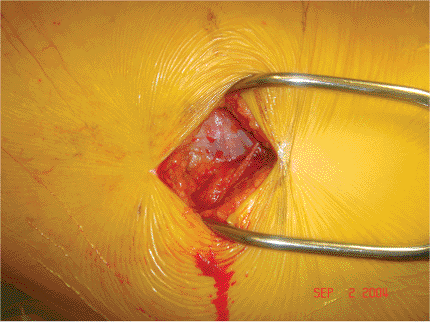

to the greater trochanter and extending distally in line with the

femoral shaft (Fig. 16.7). The length of the

incision depends upon the patient’s size. The iliotibial band is

exposed and incised in line with its fibers (Fig. 16.8). The vastus lateralis is elevated from the intermuscular septum and the lateral aspect

of the proximal femur dissected of soft tissue (Fig. 16.9).

![]() |

Figure 16.7.

A straight 3- to 4-cm lateral incision is initiated just distal to the greater trochanter and is extended distally in line with the femoral shaft. |

Figure 16.8. Exposure of the iliotibial band.

|